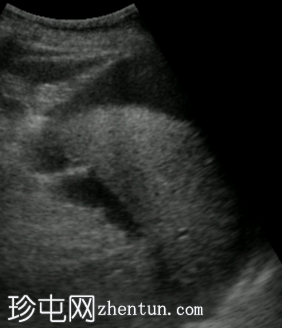

斜向

超声图像显示右上腹肝脏周围存在均匀的无回声区域。左上腹脾脏附近也存在类似的无回声区域,肠管之间的盆腔内也存在无回声区域。这些积液的总体积估计为3-4升。胆囊外观未见异常,无结石或壁增厚的迹象。由于上覆肠道气体和患者体型特征,胰腺肿块未能清晰显示。